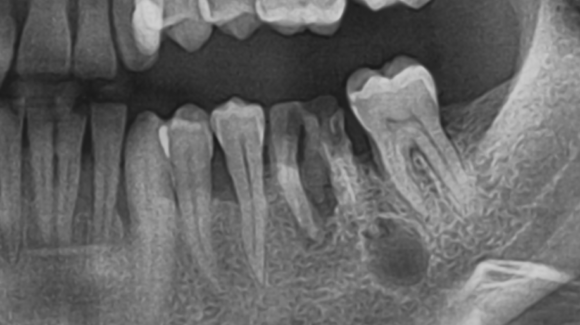

Intraorális röntgen – kis röntgen

A röntgen készítésekor a filmet a páciens szájában helyezik el. Ez a fajta röntgen 2-3 fogat képes, akár teljes hosszában leképezni. Láthatóvá válnak a gyökércsatornák, a gyökércsúcs körüli elváltozások, de akár még a csontszerkezet is.

• Periapicalis felvétel: Ezeket elsősorban gyökérkezelések során alkalmazzuk, a gyökér csúcsáról és a környező terület állapotáról ad pontos képet.

Intraorális röntgen és panoráma röntgen elemzése során is rábukkanhatunk gyanús, kezelésre szoruló fogakra.

Lyukas fog röntgen képe:

A szuvasodás jellemzően sötét, homályos üregként köszön vissza a fog koronai részén. Az egységesen világosszürke vagy „fehér” színű fogakon fekete, sötét foltok láthatók.

Fogciszta röntgen felvételen:

A leggyakrabban általában a foggyökér csúcsa környékén fedezhetők fel a gócnak számító ciszták. A fogcisztának saját burka van, így a képeken élesebb határral rendelkező kisebb vagy nagyobb gombócnak tűnik.

A foggyökér gyulladás röntgen képe:

A gyulladás az egészséges csontszövettől sötétebb foltként jelenik meg, jellemzően szintén a gyökér körüli területen.